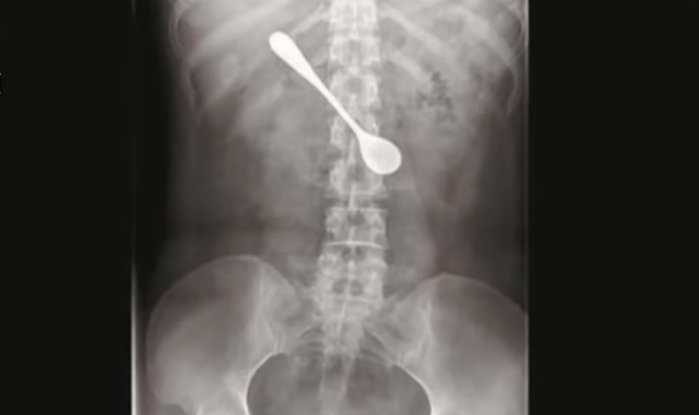

Elle avale une cuillère en tentant de déloger une arête coincée dans sa gorge

Une femme s’est retrouvée avec une cuillère de 13 cm coincée dans l’estomac, après avoir tenté de déloger une arête bloquée dans sa gorge.